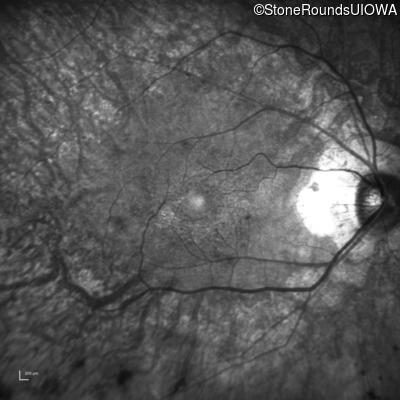

Visit at age: 58 years

Infrared Fundus Photograph - Right - 20/25 -3

Exemplar